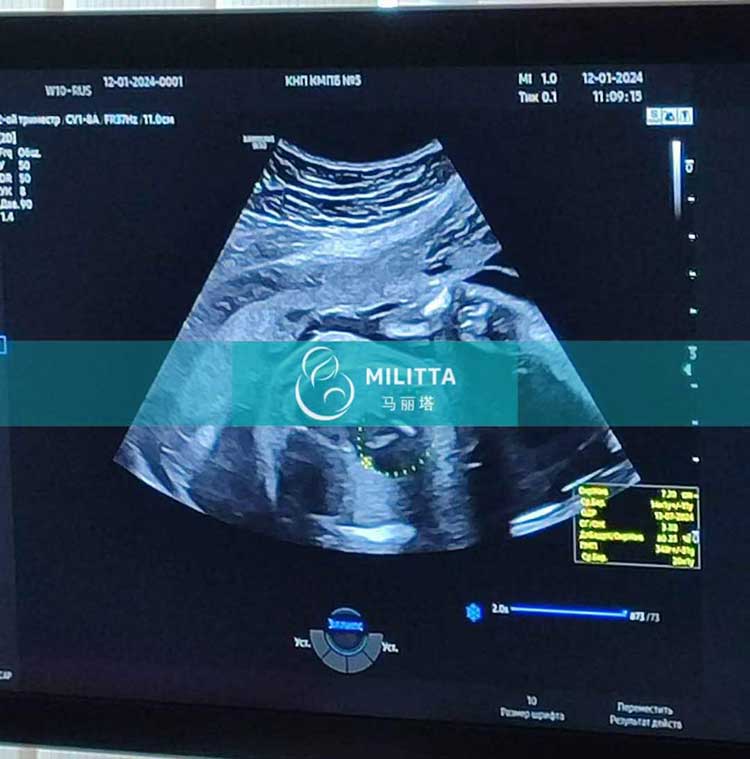

乌克兰丽塔医院的试管妈妈做23周+四维彩超孕检

陪着乌克兰LITA的爱心妈妈来做四维彩超孕检,胎儿已经23周+,检查身体发育正常,辛苦妈妈了